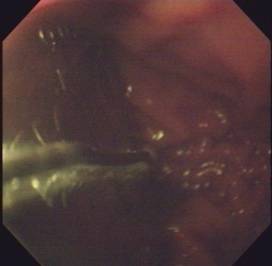

3.內鏡和細胞學檢查對本病的診斷幫助不大,但可用於本病與食管賁門癌等病之間的鑑別診斷。